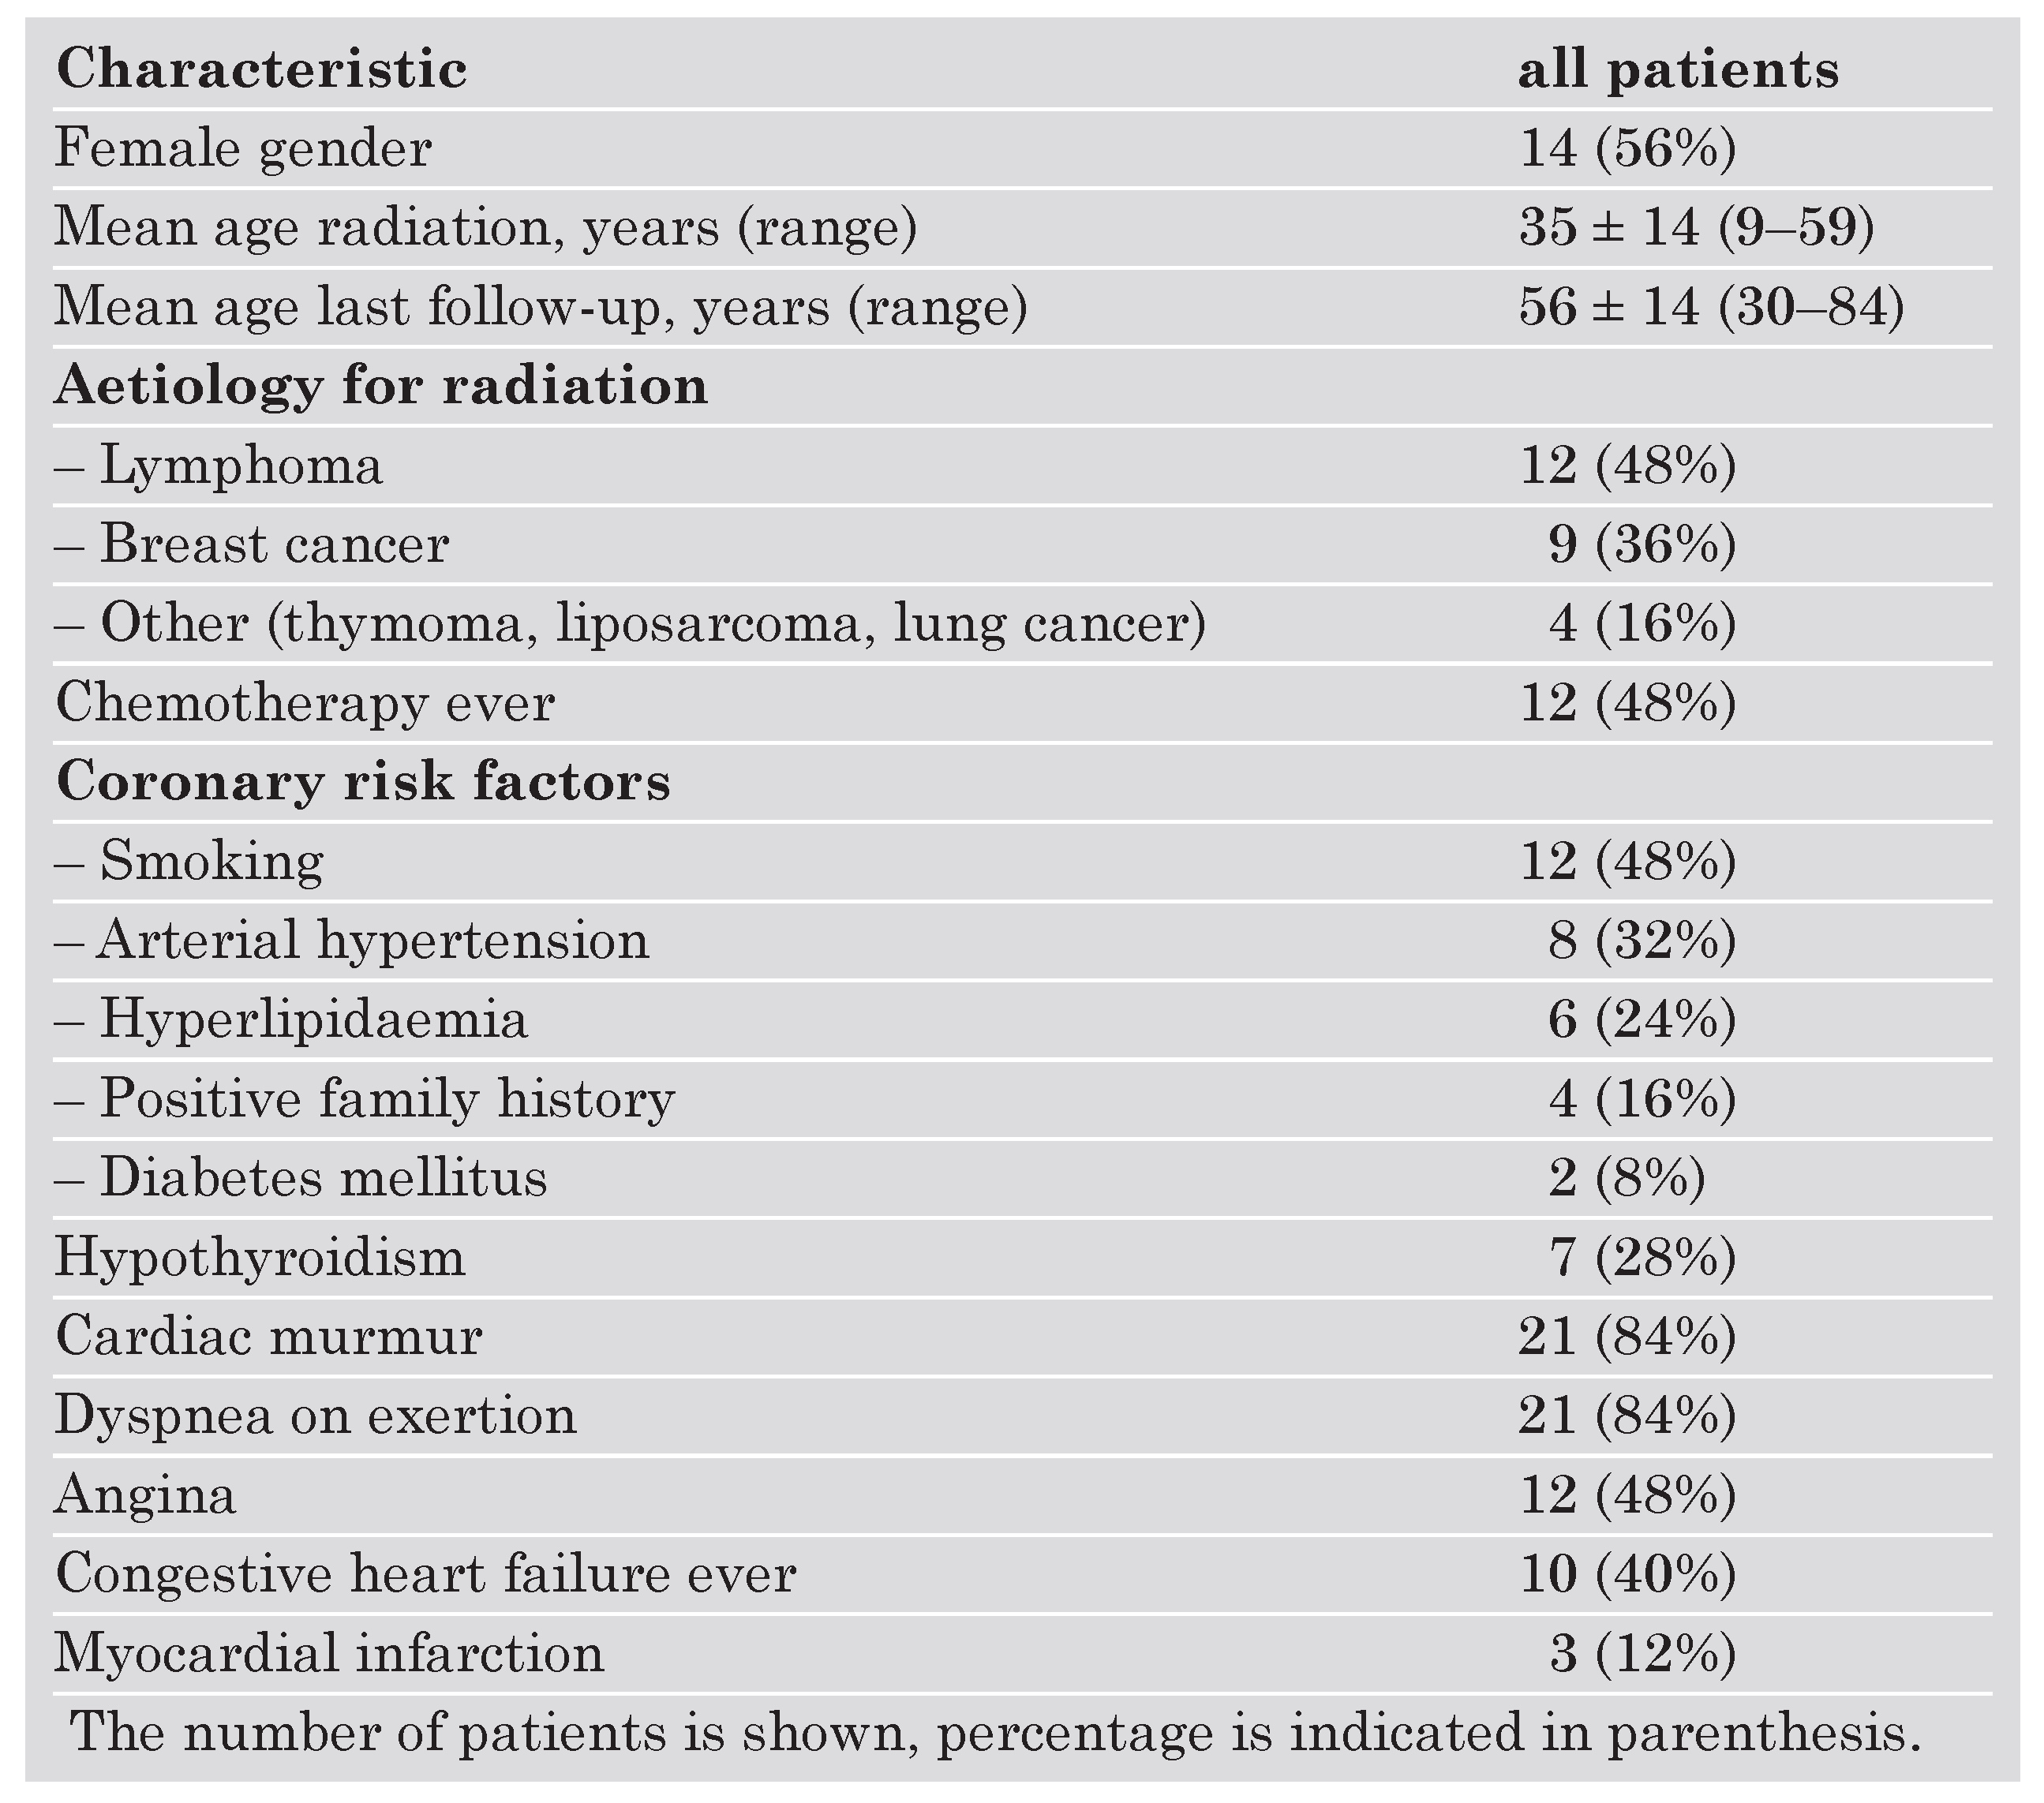

Clinical characteristics

|